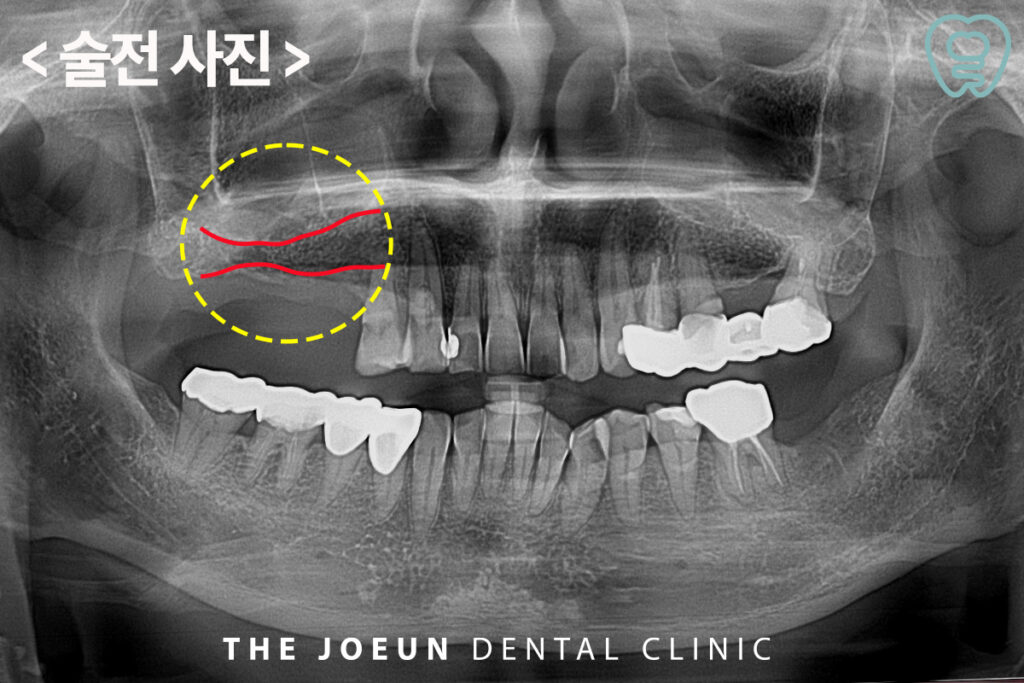

환자분께서는 오른쪽 위 어금니를 타 치과에서 발치하시고 임플란트를 진행하고 싶으시다며 내원해 주셨는데요. 발치를 하신 지 시간이 꽤 지났다고 말씀해주셨지만 기존의 잇몸 염증으로 인해 잇몸뼈가 임플란트 식립을 하기에는 부족하였고, 상악동이 아래로 내려와 있어 상악동 거상술을 동반한 임플란트 식립 계획을 수립하게 되었습니다.

당일 바로 상악동 거상술과 임플란트 식립을 진행하였는데요. 치조정 접근을 통한 상악동 거상술을 함께 진행하였습니다.